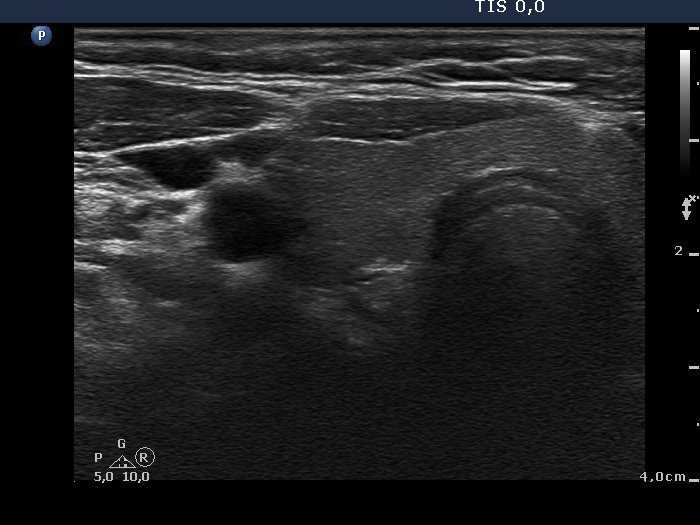

Clinical data: A 63-year-old woman was referred for exact localization of a parathyroid before surgery. The patient had diffuse complaints, including fatigue, depression, weight loss. On routine laboratory blood test, an elevated serum calcium level, thereafter an elevated parathormone level (154 pg/mL) were detected. MIBI scintigraphy disclosed parathyroid adenoma corresponding to the right lower parathyroid.

Ultrasonography. The thyroid was minimally hypoechoic and had several insignificant hypoechoic lesions. There was a solid-cystic mass dorsal to the lower pole of the right lobe.